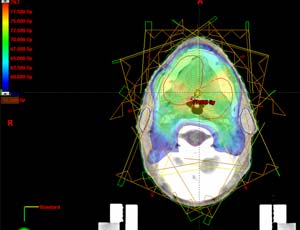

Advanced form of three dimensional conformal radiation therapy.

Intensity modulated radiation therapy (IMRT) refers to radiotherapy technique on which nonuniform dose distribution across the field is delivered from any given position of the treatment beam.